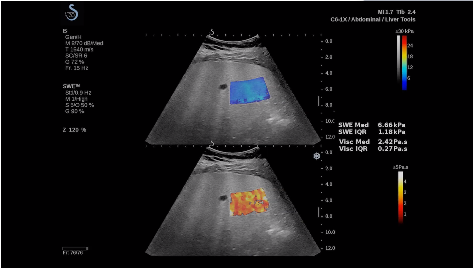

法國(guó)聲科影像(SuperSonic Imagine,SSI. Euroniex:FR0010526814)近日發(fā)表公告,宣布其研發(fā)的新一代“極速”超聲成像平臺(tái)(UltraFast Imaging),首次實(shí)現(xiàn)了肝臟的多項(xiàng)超聲定量評(píng)估新指標(biāo)同步檢測(cè),包括:Att PLUS,SSp PLUS和Vi PLUS等,基本涵蓋肝臟相關(guān)病理變化指征的如纖維化、脂肪變、炎癥等。據(jù)悉,此多項(xiàng)新技術(shù)新將搭載于新Aixplorer系列E超系統(tǒng)。

法國(guó)聲科影像公司(SuperSonic Imagine. SA,F(xiàn)rance),2005年由三位諾貝爾獎(jiǎng)級(jí)科學(xué)家主導(dǎo)創(chuàng)立,專(zhuān)注于E超的開(kāi)發(fā)和生產(chǎn),是目前世界上唯一可以同時(shí)應(yīng)用兩種波進(jìn)行人體檢測(cè)的系統(tǒng):縱波形成高質(zhì)量的二維組織結(jié)構(gòu)圖像,而橫波可以使醫(yī)生實(shí)時(shí)準(zhǔn)確地看到并分析組織的硬度,有效減少有創(chuàng)檢查、避免損傷。

E超相關(guān)技術(shù)已被多項(xiàng)多中心大樣本研究證實(shí)對(duì)于肝纖維化無(wú)創(chuàng)評(píng)估有重要意義,同時(shí)也可全面應(yīng)用于乳腺、甲狀腺、肝臟、前列腺、肌骨、婦科等全身各組織器官的定量評(píng)估和鑒別診斷。在慢性肝臟方面,聲科E超的肝臟相關(guān)定量診斷技術(shù)集,于2018年獲得美國(guó)FDA認(rèn)證,成為FDA歷史上首次獲批的單病種超聲全面定量解決方案。

E超是在原有B超、彩超(彩色多普勒CDFI)基礎(chǔ)上研發(fā)成功的新一代超聲剪切波彈性成像系統(tǒng),是一種能夠全面應(yīng)用于表淺組織、腹部臟器,血管等方面的組織彈性成像技術(shù)。根據(jù)組織硬度彈性值的不同,有效鑒別實(shí)性腫瘤的良惡性。對(duì)于惡性病變的診斷具有較高的特異性和敏感性,尤其對(duì)于甲狀腺、乳腺、前列腺等小器官,能夠完成常規(guī)超聲不能完成的組織定量分析,可以實(shí)時(shí)、全幅、全定量獲得組織彈性(硬度)信息,為鑒別腫瘤的良惡性提供客觀、量化的診斷依據(jù)。